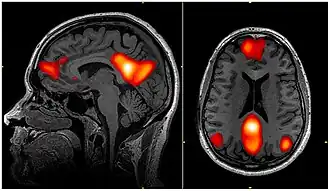

![]() fMRI scan showing regions of the default mode network; the dorsal medial prefrontal cortex, the posterior cingulate cortex, the precuneus and the angular gyrus | |

In neuroscience, the default mode network (DMN), also known as the default network, default state network, or anatomically the medial frontoparietal network (M-FPN), is a large-scale brain network primarily composed of the dorsal medial prefrontal cortex, posterior cingulate cortex, precuneus and angular gyrus. It is best known for being active when a person is not focused on the outside world and the brain is at wakeful rest, such as during daydreaming and mind-wandering. It can also be active during detailed thoughts related to external task performance.[3] Other times that the DMN is active include when the individual is thinking about others, thinking about themselves, remembering the past, and planning for the future.[4][5] The DMN creates a coherent "internal narrative" central to the construction of a sense of self.[6]